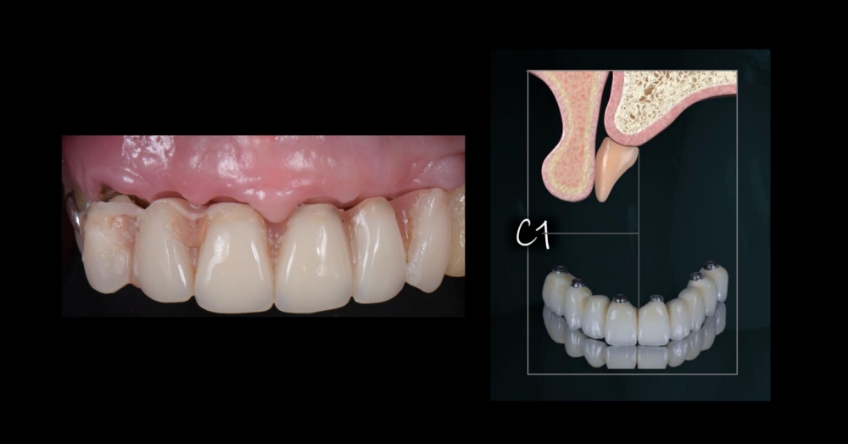

Even though there were only three remaining teeth, they were so severely compromised that they were hopeless; however, their presence, as well as the support provided by the flipper type of removable provisional restoration, helped enormously in preserving a rather pleasing gingival architecture, which would be destroyed if we chose a fixed-hybrid restoration.

This makes her a lip-tooth-ridge Class I patient according to the published classification. According to Dr. Mish’s classification, she is an FPI, which means her preexisting condition is conducive for an all-white, implant-supported fixed dental prosthesis without any pink ceramics.

Ultimately, the patient was treated using a combination of traditional and zygomatic implants, allowing her to transition into the definitive prosthesis uneventfully and in a reasonable time frame. This prosthetic design aimed to improve the distribution of occlusal forces and provide enhanced structural support for the final prosthesis.